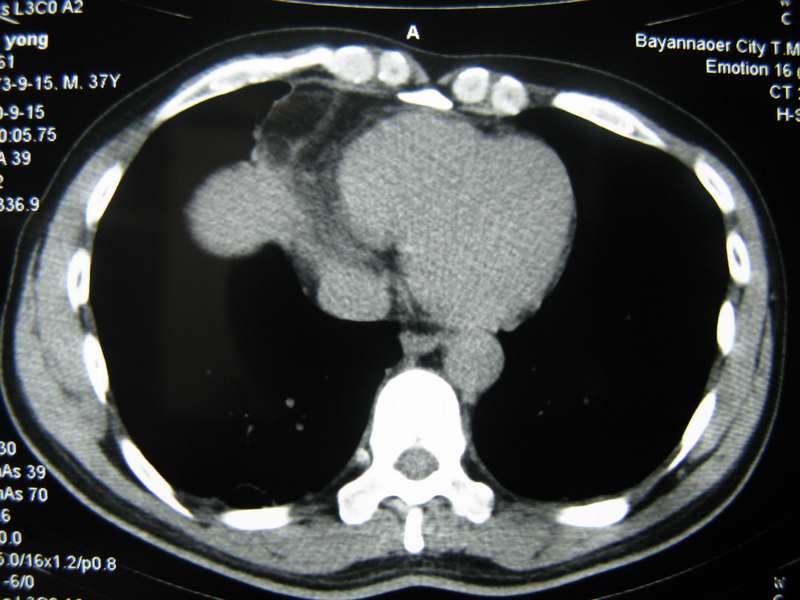

男,37岁,主述胸疼厉害,无咳嗽,无发热,血象也不高,病灶内ct值脂肪密度,右侧胸腔内少量积液,同道们考虑什么?谢谢!

脂肪垫,右下肺感染,少许积液是症状所在

纵膈脂肪堆积,右肺慢性炎症。

两肺下叶基底段纤维灶,右肺下叶基底背侧相应胸膜肥厚,右肺中叶内侧段部分不张。前中下纵隔团块状脂肪影,随访除外胸腺脂肪瘤。

不除外膈疝。